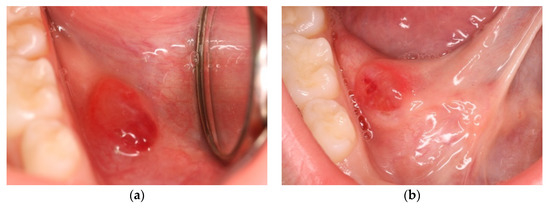

- Incision. Soft tissue incisions with microsurgical scissors to remove the pseudocystic dome and provide adequate access to the area of interest.

- Probing and irrigation. The lumen of the lesion was probed, irrigated with sterile saline solution, and dried with cotton gauze.